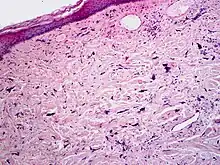

Micrograph of pleomorphic fibroma. Cell-depleted, fibrous connective tissue with atypical fibroblasts